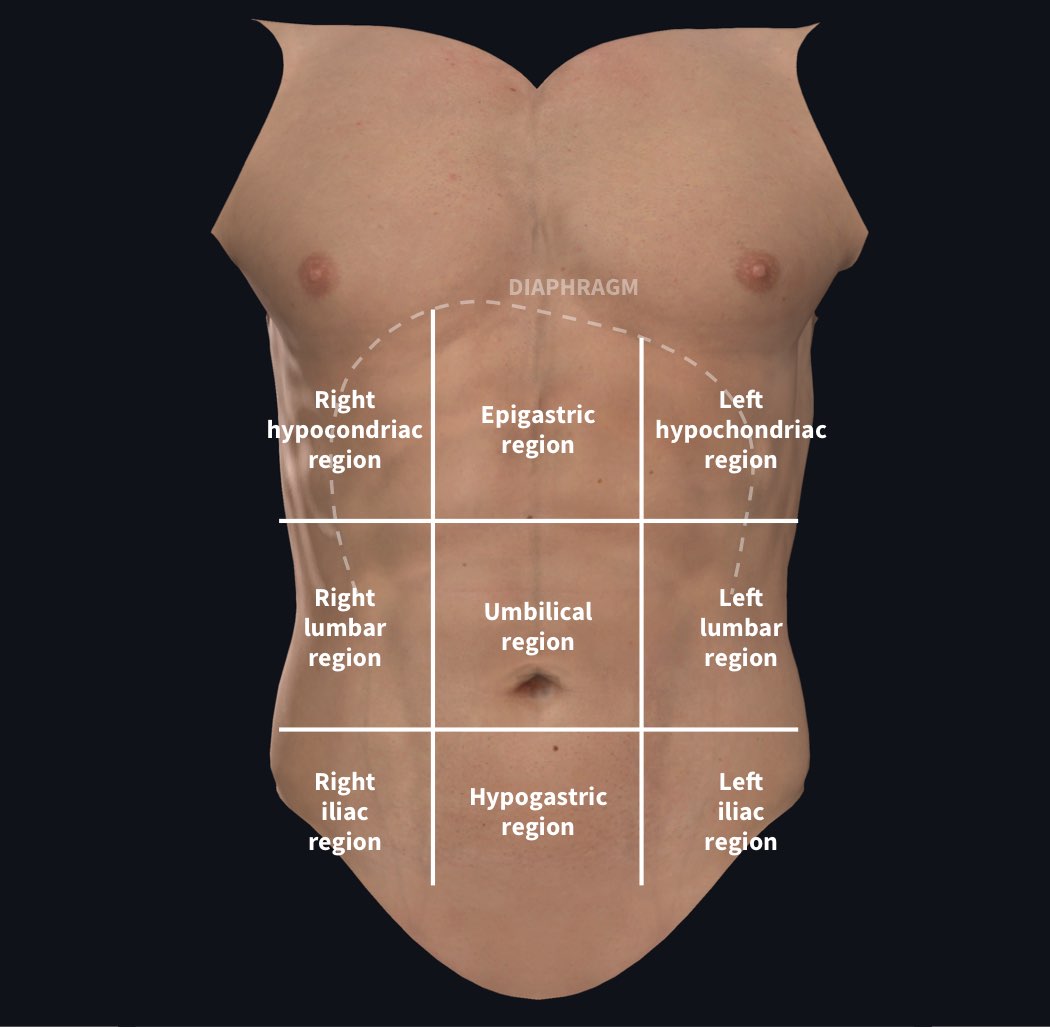

www.alamy.comAbdomen - Wikipedia, La Enciclopedia Libre

www.alamy.comAbdomen - Wikipedia, La Enciclopedia Libre

es.wikipedia.orgabdomen organs stomach abdominal internal organ rib locations ribs cage spinal projections labeled spine navel anatomical lumbar

es.wikipedia.orgabdomen organs stomach abdominal internal organ rib locations ribs cage spinal projections labeled spine navel anatomical lumbar

guidelibmisjoinder.z22.web.core.windows.netUnderstanding Abdominal Divisions | Anatomy Snippets | Complete Anatomy

guidelibmisjoinder.z22.web.core.windows.netUnderstanding Abdominal Divisions | Anatomy Snippets | Complete Anatomy

completeanatomy.cnAbdomen (Human Anatomy) - Image, Definition, Function, Diseases And More

completeanatomy.cnAbdomen (Human Anatomy) - Image, Definition, Function, Diseases And More